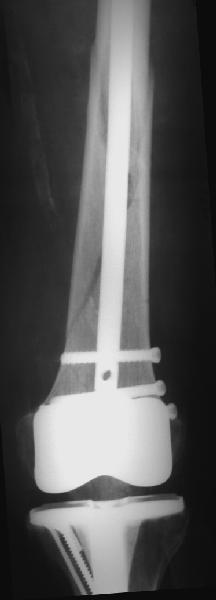

В приложении - недавний перипротезный перелом.